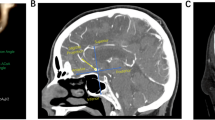

In the training set, morphological and clinical features were compared between the ruptured (147 aneurysms) and unruptured groups (357 aneurysms). The results were summarized in Table 2. Of the 21 features, 15 were selected as candidates for multiple logistic regression (P < 0.1). They were Compactness1, Compactness2, SurfaceVolumeRatio, Sphericity, SphericalDisproportion, Elongation, Flatness, Age, Sex, Hypertension, Hyperlipemia, Smoking, Drinking, Multiple aneurysms, and Location of the aneurysm. These Features were taken into multiple logistic regression and backward stepwise regression was employed to solve colinearity and construct the final model. The model was plotted as a nomogram shown in Fig. 1. Features enrolled in the nomogram included: SurfaceVolumeRatio, Flatness, Age, Hyperlipemia, Smoking, Multiple aneurysms, and Location of the aneurysm.

Nomogram for predicting aneurysm rupture risk. To calculate the rupture risk of an aneurysm, first determine the value for each feature by drawing a vertical line from that feature to the points scale. Then sum up all the individual values and draw a vertical line from the total points scale to the probability at the Diagnostic Probability line to obtain the rupture risk estimates.